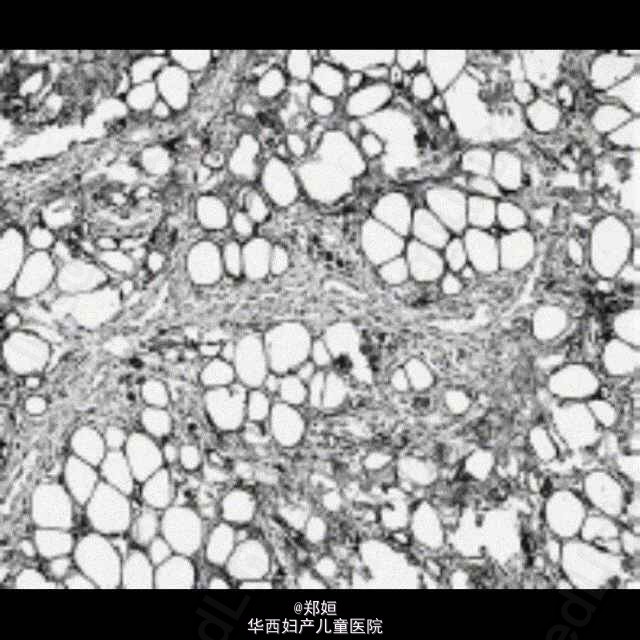

50岁女性,外阴无疼痛性膨胀数月

查体后初步诊断为外阴血管粘液瘤

初步诊断为外阴血管粘液瘤 行肿瘤的局部切除

恢复良好,无复发 外阴血管肌纤维母细胞瘤是发生于外阴、会阴及腹股沟区的具有一定临床病理特征的浅表软组织肿瘤。较为少见。血管肌纤维母细胞瘤发病比较隐匿,常常是患者无意中发现外阴肿物,病程数月至数年,一般无疼痛。肿物大多位于大阴唇和外阴区,肿瘤边界清楚。本病很少能在术前做出明确诊断,肿物局部切除可治愈,一般不复发。